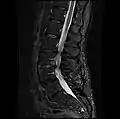

MRI lumbar spine with degeneration, post-hemilaminectomy L4-5 (sagittal T2 FRFSE)